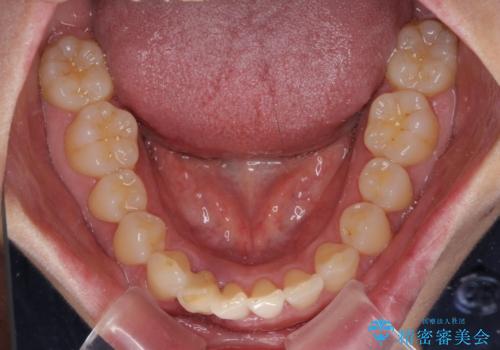

- 下顎前歯が抜けそうとのことで来院された患者様です。

初診の状態ではすぐにでも抜けそうな状態で、インプラントによる補綴治療を行うこととしました。

インプラント治療に際し、前歯の叢生に対する矯正治療を提案したところ、興味を持たれたので、インビザライン・ライトによる矯正治療を行うこととしました。

抜歯後にスペースができると恥ずかしいため、抜歯した歯を接着剤で固定した上で矯正治療を行い、その後インプラントやオールセラミッククラウンの装着を行うこととしました。